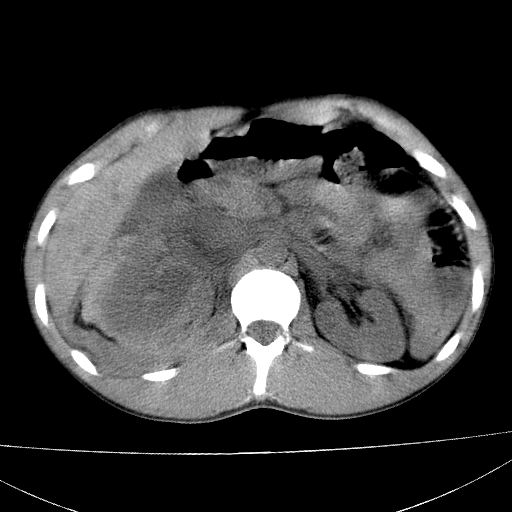

标题: CT15860:男,21岁,腹部外伤2小时伴胸疼。 [打印本页]

标题: CT15860:男,21岁,腹部外伤2小时伴胸疼。

b超示:肝破裂。

肝脏及肾脏明显有损伤性改变并激发腹腔内积液(血),以肝脏撕裂及肾周积血显著。

1)肝破裂伴腹腔积液(血)。2)右肾破裂伴右肾包膜下及肾周血肿。3)腹部空腔脏器穿孔可能。4)右侧少量胸腔积液(血)。

1)肝破裂伴腹腔积液(血)。2)右肾破裂伴右肾包膜下及肾周血肿。3)右侧少量胸腔积液(血)。

肝肾挫裂伤,右肾周及包膜下血肿,腹腔积液,不排除空腔脏器穿孔,建议行增强检查

肝、右肾包膜下血肿,右侧腰大肌及腹膜后血肿;腹腔少量积血;腹腔疑有少量游离气体伴肠破裂。

1肝挫伤伴腹腔积液。2右肾挫裂伤伴右肾包膜及肾后间隙肿血肿。3右肾脏周围的积气,十二指肠显示结构不清,考虑十二指肠降部破裂可能性大。